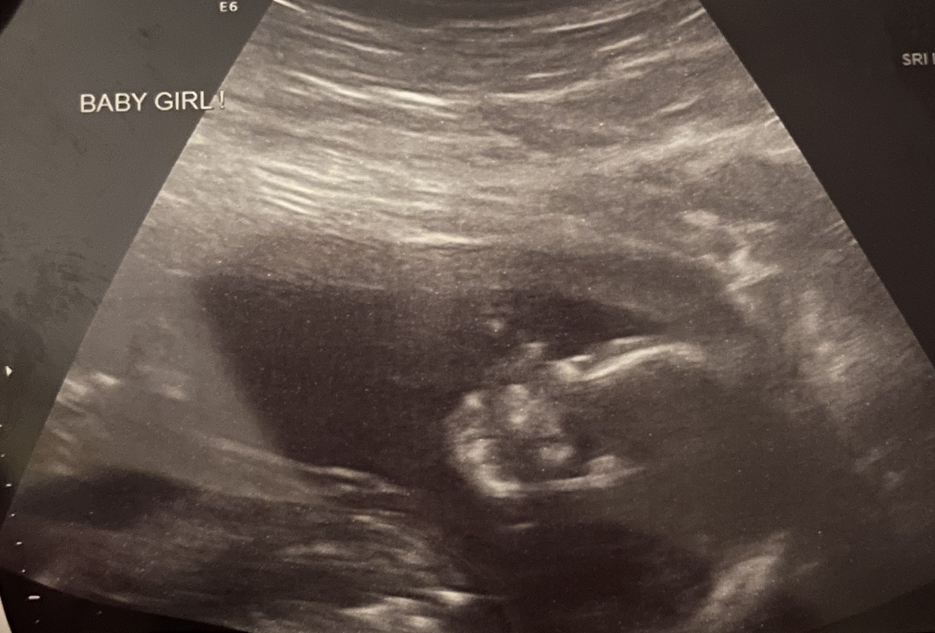

Here’s a pic of my sweet baby girl 💖